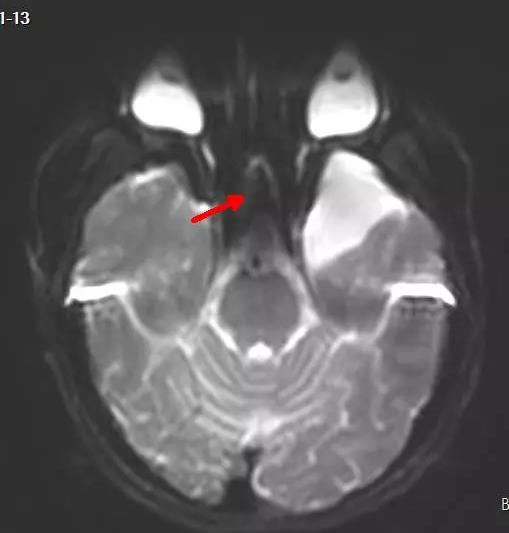

年仅15岁的花季少女小睿(化名)于4年前在家乡医院检查时发现脑子里面长了一个囊肿(图3),虽经多家医院诊治,但家属对是否手术治疗仍拿不定主意。经当地医生推荐,家属带着小睿找到了郑州大学五附院神经外科学科带头人王新军教授。王新军教授仔细评估后认为小睿目前没有明显症状,可以先观察暂不做手术,日后定期随访,这一随访就是4年。随访过程中,小睿出现了癫痫发作,并且有说话不流利,理解能力下降的症状,于是在家属陪同下于近日再次来到郑州大学五附院。王新军教授带领付旭东主任及其团队对小睿进行了详细的影像学检查及癫痫定位评估,制定了周密的手术方案。手术由王新军教授亲自主刀、付旭东主任及其团队配合,通过术中监测确定癫痫病灶(图4),切除蛛网膜囊肿,术后再次监测确保癫痫灶切除彻底。在麻醉科及癫痫定位室医务团队的鼎力支持下,手术顺利,切除蛛网膜囊肿的同时也切除了癫痫病灶。术后小睿恢复很快,癫痫未再发作,言语功能也明显改善。

图3 左颞叶蛛网膜囊肿 红箭头所指